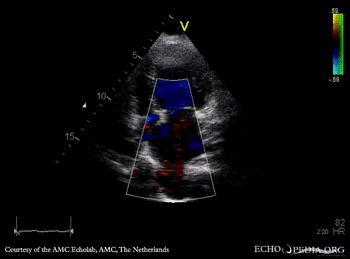

| Courtesy of: AMC Echolab, AMC, The Netherlands | |

| A4CH: dilated pulmonary veins | A4CH with Color Doppler |